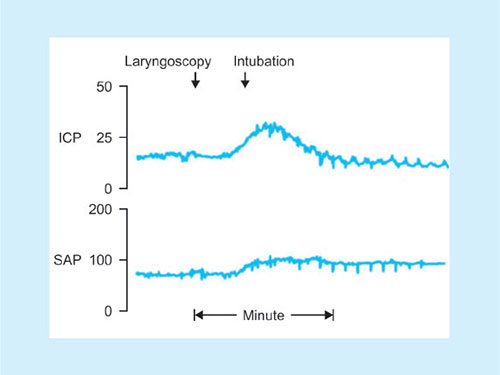

Elevation of ICT/IOP.

Fig. 40: Response to tracheal intubation.Source: Bedford RF: Circulatory responses to tracheal intubation. Probl Anesth.

Increases in systemic arterial pressure (SAP) and intracranial pressure (ICP) in response to endotracheal intubation in a patient with a small brain tumor. Notice the minimal response to rigid laryngoscopy. There is a sustained increase in systemic arterial pressure but only a transient increase in ICP, which returns to normal as cerebrovascular autoregulation becomes operative.